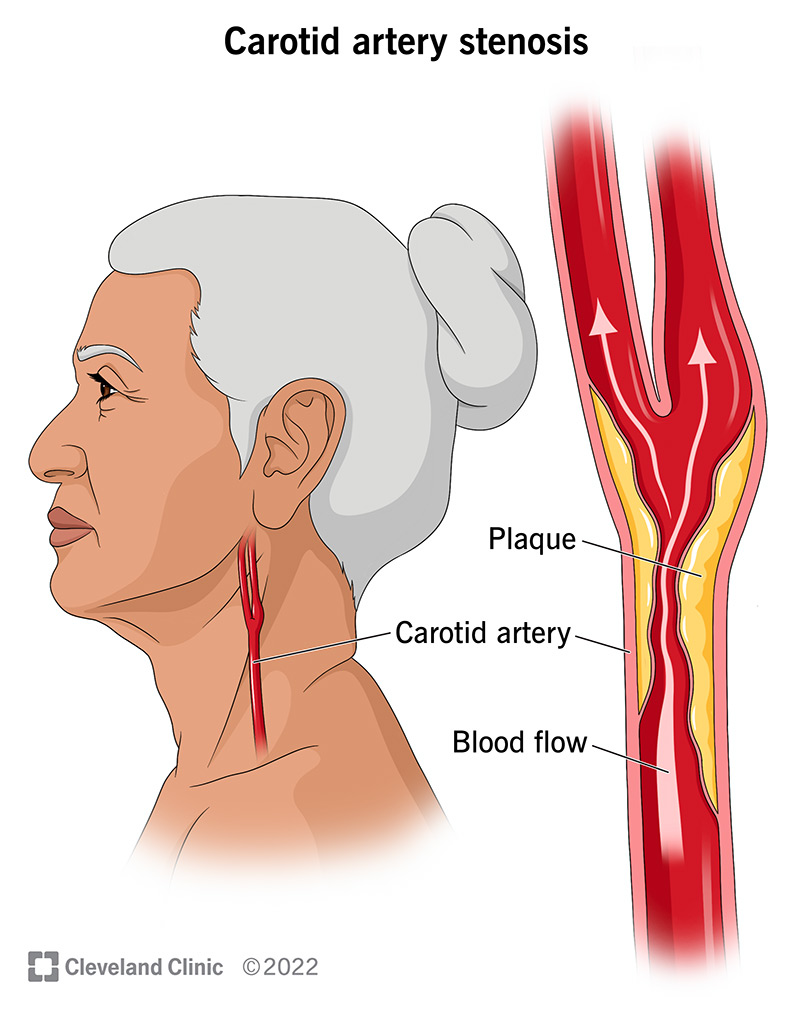

Carotid Artery Stenosis Wikidoc

Carotid Artery Stenosis Wikidoc